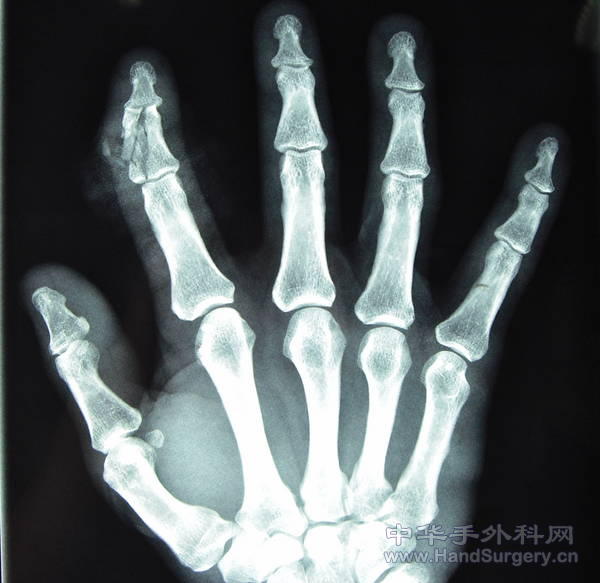

骨折你这样内固定还敢做这个筋膜瓣,真厉害,希望你把术后成活的照片补上来!谢谢!

我看那个创面皮肤成锯齿状血运应该很好。好像没有缺损吧。不可以真接缝上吗。。我们这边锣刀割伤的比这还碎,一般成活都没问题。再说底下是钢板,再铺筋膜蒂植皮打包风险比较高吧。还不如做同指的筋膜蒂皮瓣。个人愚见。

呵呵,如果你不是选择上钢板的话,可能可以直接缝合了,筋膜瓣加植皮易引起挛缩,另外这个钢板放在这里是不是会影响伸指肌腱的功能啊,楼主应加强随访!皮瓣切取思路不错的,学习了